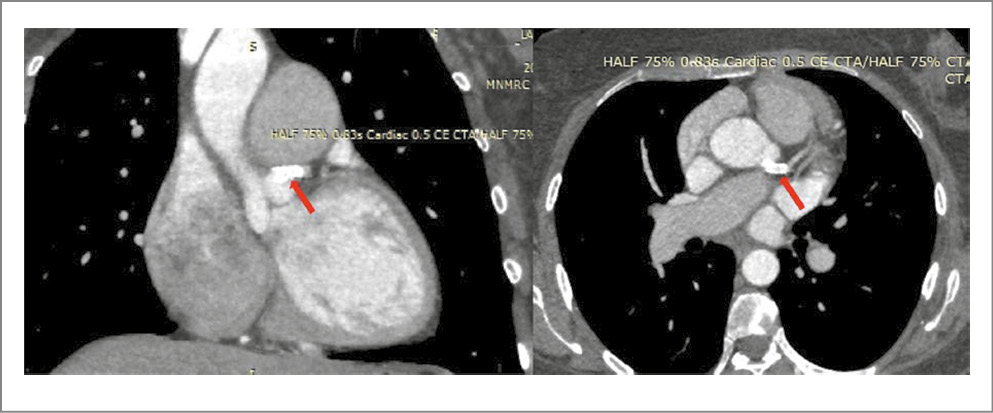

По данным контрольной КТ-коронарографии (25.03.2022) также отмечено отсутствие рестеноза в стентированном сегменте (рис. 4).

Рис. 4. КТ-коронарография. Зона стентированного сегмента ствола ЛКА отмечена красной стрелкой.